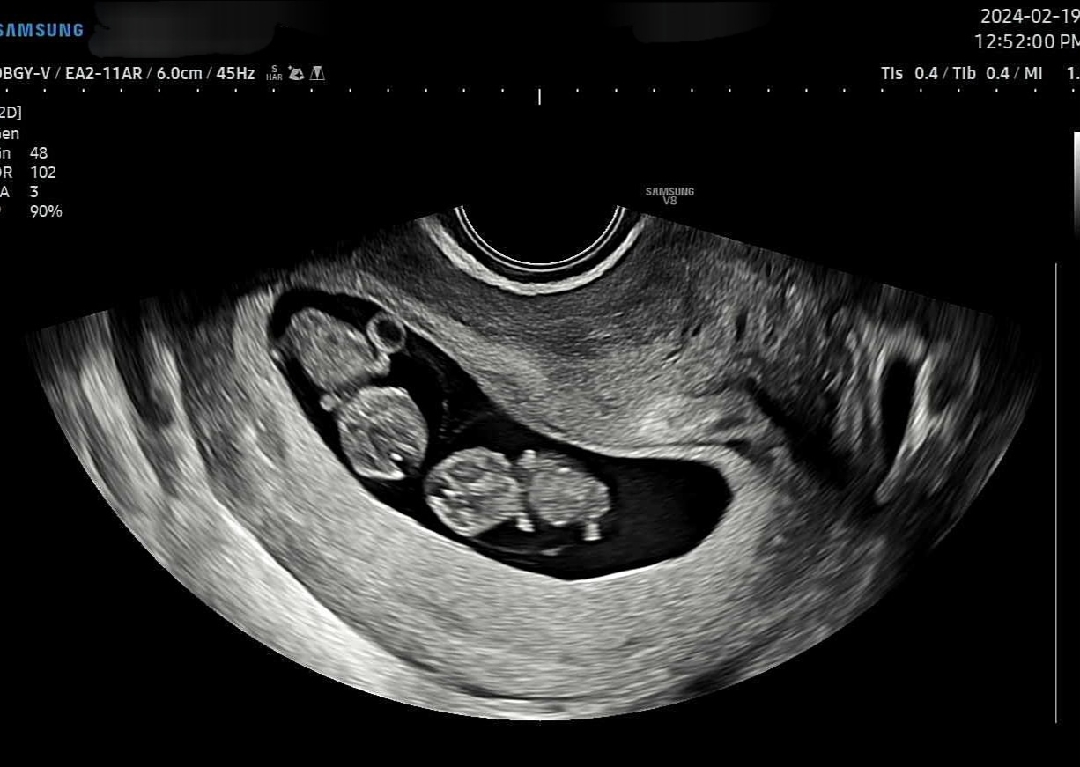

9주차인 일란성 젤리곰둥이들 기여워서 올려봅니당,, 🤭